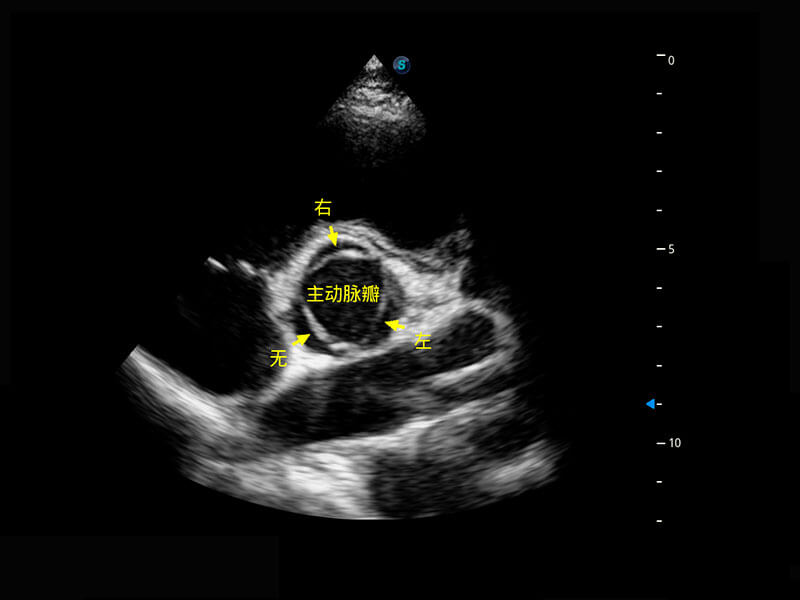

P60搭载一系列胎儿心脏成像技术,实现精细的胎儿心脏评估。

四腔切面

四腔心血流

右室双出口

胎心容积成像